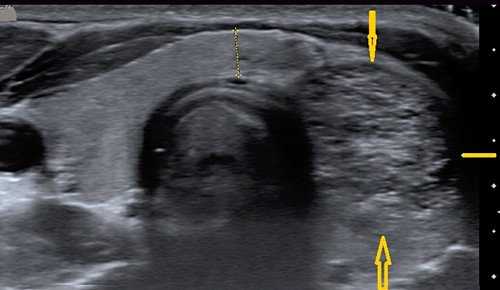

(Слева) УЗИ, поперечная проекция: в щитовидной железе у пациента с тиреоидитом Хашимото визуализируются множественные эхогенные горизонтальные линии, представляющие фиброзные перегородки. У пациентов с хроническим заболеванием необходимо исключить неходжкинскую лимфому и любые подозрительные узлы.

о Типичные фиброзные перегородки при хроническом заболевании в виде множественных эхогенных горизонтальных линий

о Диффузное снижение эхогенности и неоднородная микронодулярная эхоструктура